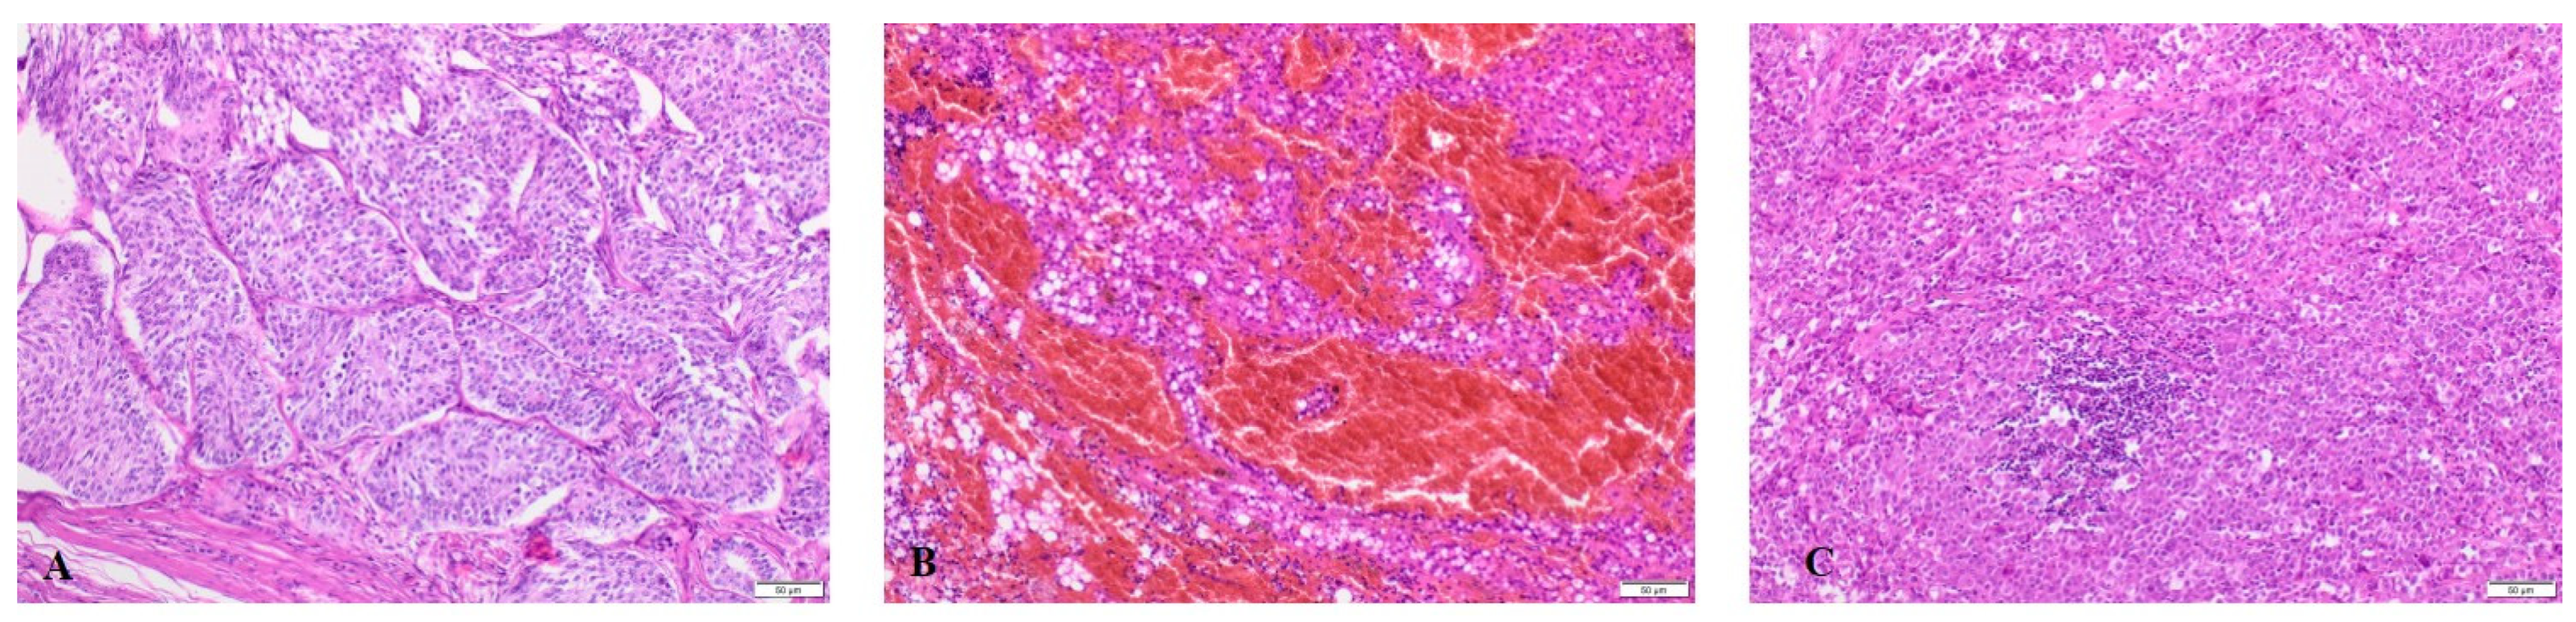

2.1. mtDNA Changes in TTs

4.1. Samples

4.2. Patient Eligibility

4.3. Sample Information

4.4. Histopathology